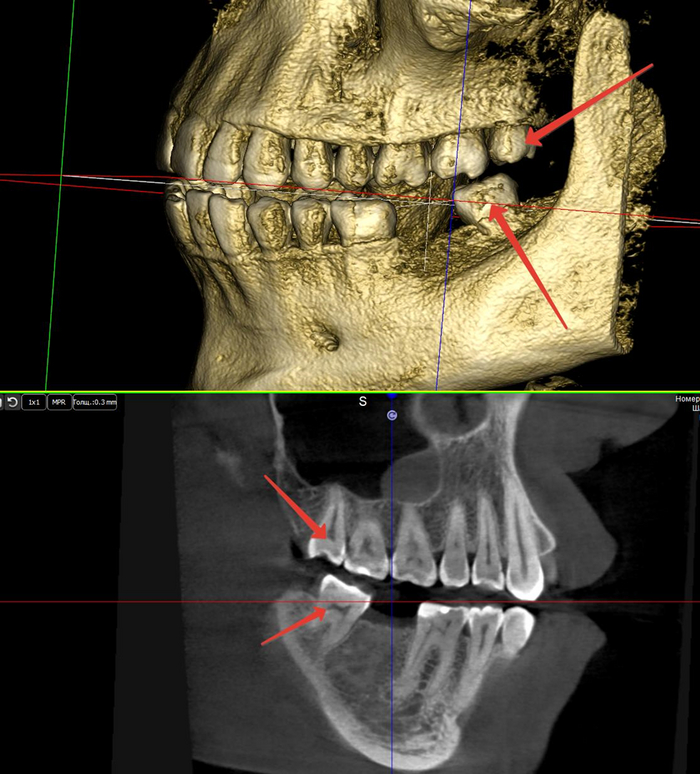

После того, как мы сделали анестезию, мы по необходимости производим разрез и отслаиваем слизистую оболочку с надкостницей от кости (слизисто-надкостничный лоскут) и бормашиной с водяным охлаждением выпиливаем костную стенку. Почему по необходимости? Потому что эти этапы зависят от степени прорезанности и расположения зуба. Чем более прорезан зуб, тем меньше разрез и меньше убираем кости. Иногда обходимся одним разрезом, иногда даже разрез не приходится делать, а просто распиливаем зуб. Короче, смотрим по ситуации.

По необходимости распиливаем сам зуб. Опять по необходимости? Конечно! Ведь надо смотреть по ситуации и соблюдать баланс между травматичностью и скоростью проведения операции. Если зуб лежит только под слизистой, корни сросшиеся и его можно достать элеватором, то не надо лишний раз его пилить. Достали, зашили и отпустили домой. Если же у нас зуб лежит криво и достать него просто так не получается, то тогда уже пилим либо зуб, либо подпиливаем кость.

Если у зуба растопырены корни, то их тоже надо разделять и по одному доставать, как в 30 главе.

Верхние удаляются схожим образом

Попроще

Посложнее